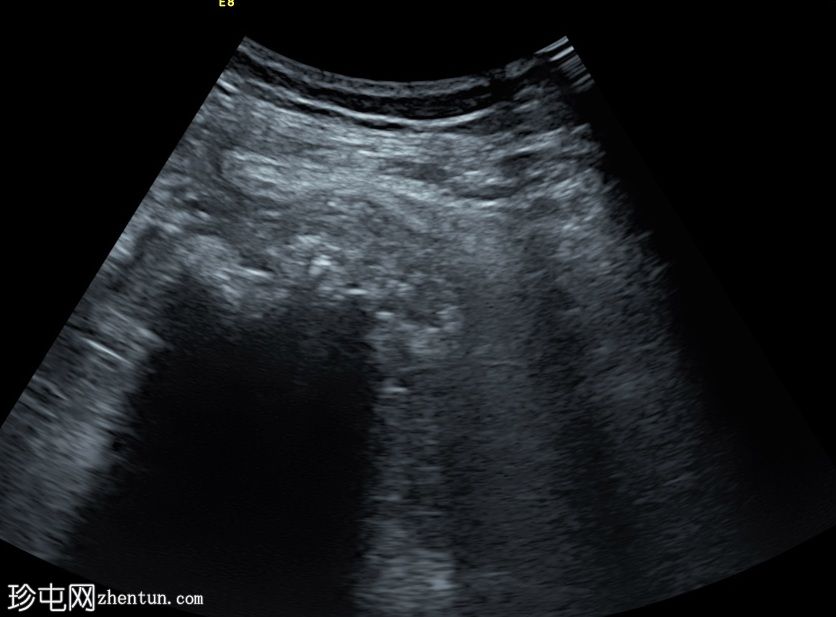

超声

纵切面

患者在局部麻醉下接受了超声引导下经左侧股骨受损皮质的活检。